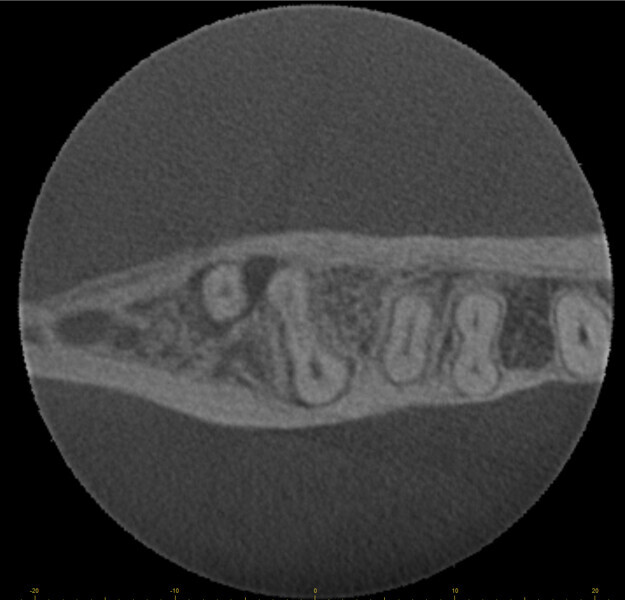

Fig. 17a: Case assisted with CBCT to determine anatomy pre-operatively. Note the multiple cross sections moving apically and the correlation to the 2-D view. Note also the conservative taper in relation to the root width. (Courtesy of Dr. Brett Gilbert)

Fig. 17b: Case assisted with CBCT to determine anatomy pre-operatively. Note the multiple cross sections moving apically and the correlation to the 2-D view. Note also the conservative taper in relation to the root width. (Courtesy of Dr. Brett Gilbert)

Fig. 17c: Case assisted with CBCT to determine anatomy pre-operatively. Note the multiple cross sections moving apically and the correlation to the 2-D view. Note also the conservative taper in relation to the root width. (Courtesy of Dr. Brett Gilbert)

Fig. 17d: Case assisted with CBCT to determine anatomy pre-operatively. Note the multiple cross sections moving apically and the correlation to the 2-D view. Note also the conservative taper in relation to the root width. (Courtesy of Dr. Brett Gilbert)

Fig. 17e: Case assisted with CBCT to determine anatomy pre-operatively. Note the multiple cross sections moving apically and the correlation to the 2-D view. Note also the conservative taper in relation to the root width. (Courtesy of Dr. Brett Gilbert)

Fig. 17f: Case assisted with CBCT to determine anatomy pre-operatively. Note the multiple cross sections moving apically and the correlation to the 2-D view. Note also the conservative taper in relation to the root width. (Courtesy of Dr. Brett Gilbert)